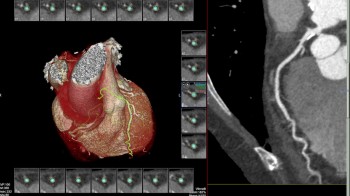

- MSCT koronarografija (prikaz krvnih žila srca CT-om, bez neugodnosti i komplikacija koje nosi klasična koronarografija), u saradnji s Poliklinkom dr.Al-Tawil